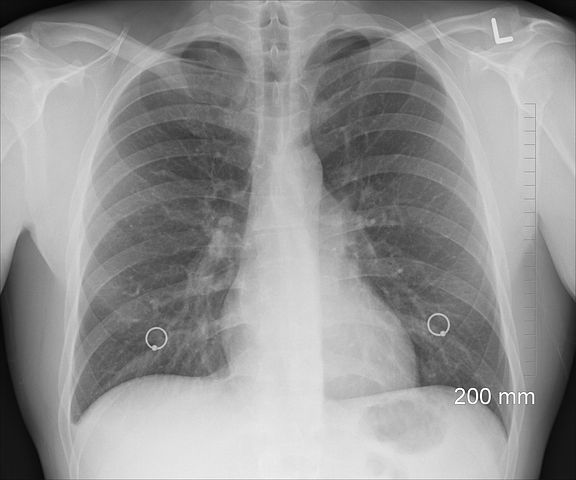

Pneumonia este o infecție respiratorie acută a țesutului plămânilor (alveoli), determinând acumulare de lichid și puroi la acest nivel. Pentru că sacii alveolari afectați sunt responsabili de schimbul de oxygen, inflamarea acestora poate împiedica umplerea lor corespunzătoare cu oxygen, ceea ce poate conduce la oxigenare insuficientă a sângelui și a organelor din corp. Din această cauză, pneumonia poate fi deosebit de periculoasă la copiii cu vârstă sub 2 ani, vârstnicii peste 65 ani, persoanele cu un sistem imunitar slăbit sau cei cu boli pulmonare cronice, cum ar fi bronhopneumopatia cronică obstructivă (BPOC) și astmul bronșic.